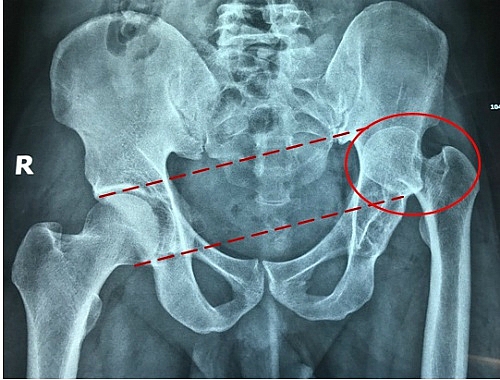

| Ảnh trước phẫu thuật với vùng ổ cối khớp háng bên trái bị biến dạng lệch lên vùng xương chậu. |

Bác sĩ Nguyễn Thành Chơn, Trưởng Khoa Chấn thương, Bệnh viện Sài Gòn ITO cho biết bệnh nhân bị trật khớp lâu năm gây biến dạng ổ cối và đầu chỏm xương đùi bị đẩy lên phía trên khung chậu. Do đó phần xương chi bệnh nhân phát triển không cân xứng với chi lành, gây ra tật chân ngắn chân dài.

"Người bệnh đã bị trật khớp hơn 30 năm, vùng xương có dấu hiệu thoái hóa nặng. Nếu không mổ sớm sẽ có nguy cơ bị thoái hóa toàn bộ ổ cối, vùng khớp quanh ổ cối, dẫn đến cứng khớp không thể cử động", bác sĩ Chơn phân tích. Việc đi đứng trên đôi chân không cân đối lâu dài có nguy cơ dẫn đến cong vẹo cột sống.